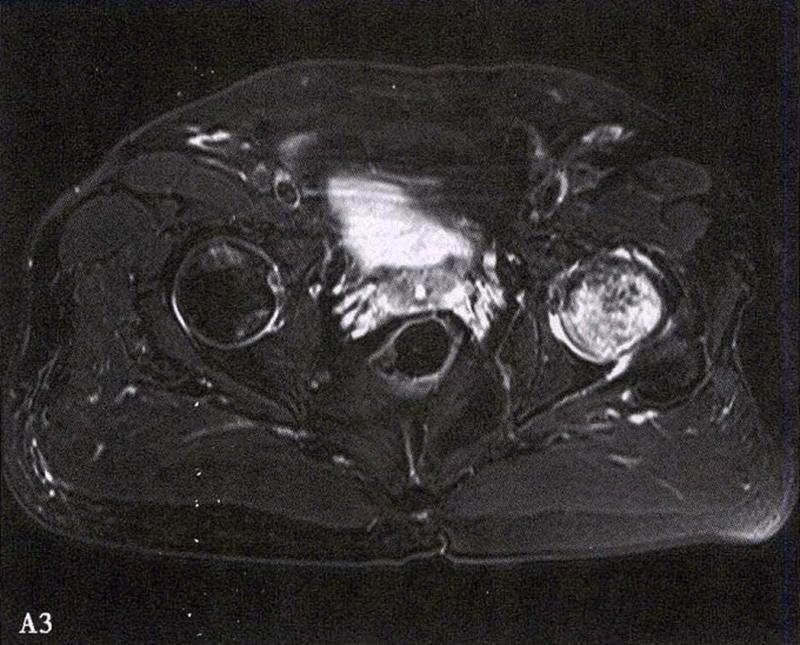

MRI示双侧股骨头坏死,冠状面显示右侧股骨头坏死(图A、C),横断面显示双侧股骨头坏死(图B、D);T1加权像(图A、B)显示硬化带为低信号,T2加权像(图C、D)显示右侧骨坏死硬化带外围高信号的骨髓水肿,左侧无骨髓水肿。

A.男性,71岁,双侧股骨头坏死,右侧Ⅰ期、左侧Ⅲ期。X线片示双侧股骨头形态可,右股骨头未见明显密度改变,左股骨头关节面下见局限性骨密度减低及增高区(A1)。MRI(T2加权像)示右股骨头内双线征,左侧不规则形混杂信号,坏死区远端骨髓水肿(A2、A3)。